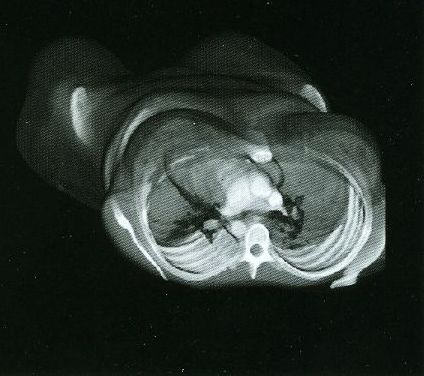

These photos of the Voxelscope II screen are typical of the types of rendering provided by the system.

Voxelscope II Screen Shots. Combination of 3-D Shaded Surface, Multiplanar Reformatting, and Segmentation

While the VPP and Voxelscopes I and II rendered "back-to-front" to implement hidden surface removal, the redesigned VoxelQ hardware was optimized for ray tracing with volume rendering capabilities. VQ projected a ray from each pixel on the display back through the object and was able to perform computations along the way. An innovative sub-voxel search algorithm rendered much more realistic surfaces using relatively simple surface shading algorithms. Even Anthony was impressed with the image quality when this technique was first simulated in software with the intent of incorporating it into the microcode - and he was most familiar what else was being done in software, which could render the best images since there were fewer time constraints. In addition to hidden surface removal and gradient shading, this approach supports various forms of transparency with perspective enabling the simulation of X-ray views ("reprojection") as well as rendering translucent organs. Many of the changes were implemented in microcode with relatively small changes to the actual hardware. But the key innovation that differentiated VoxelQ from the machines before it was the "Object Resampling Memory" (ORM) which generated tri-linearly interpolated voxel data based on full 3-D coordinates. Essentially, the eight adjacent voxels closest to the specified coordinate in the original dataset were accessed simultaneously and an interpolated result was computed auto-magically. For successive coordinates that were close together (as they would be for ray tracing), the effective throughput could approach 10 million tri-linearly interpolated voxels per second. The ORM was the only totally new custom board and replaced the MicroVAX memory.

Shading of the rendered objects is essential to the perception of 3-D depth in a static display of a single image (no stereo). Motion parallax also contributes to this but only if the update rate is high enough. The VPP only had "depth shading", whereby each pixel's value was modified by distance from the viewer. Subsequent machines used "gradient shading" which also calculated the local rate-of-change of the surface to modulate the pixel intensity. While this was not photo-realistic, the overall effect was quite satisfactory at a much lower computational cost. And with the tri-linearly interpolated voxels, the result was actually quite impressive.